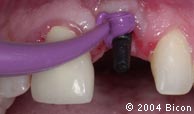

39. | 拆除临时义齿后种植体内径的 |

![]() |

40. | 插入一体化基台冠。 |